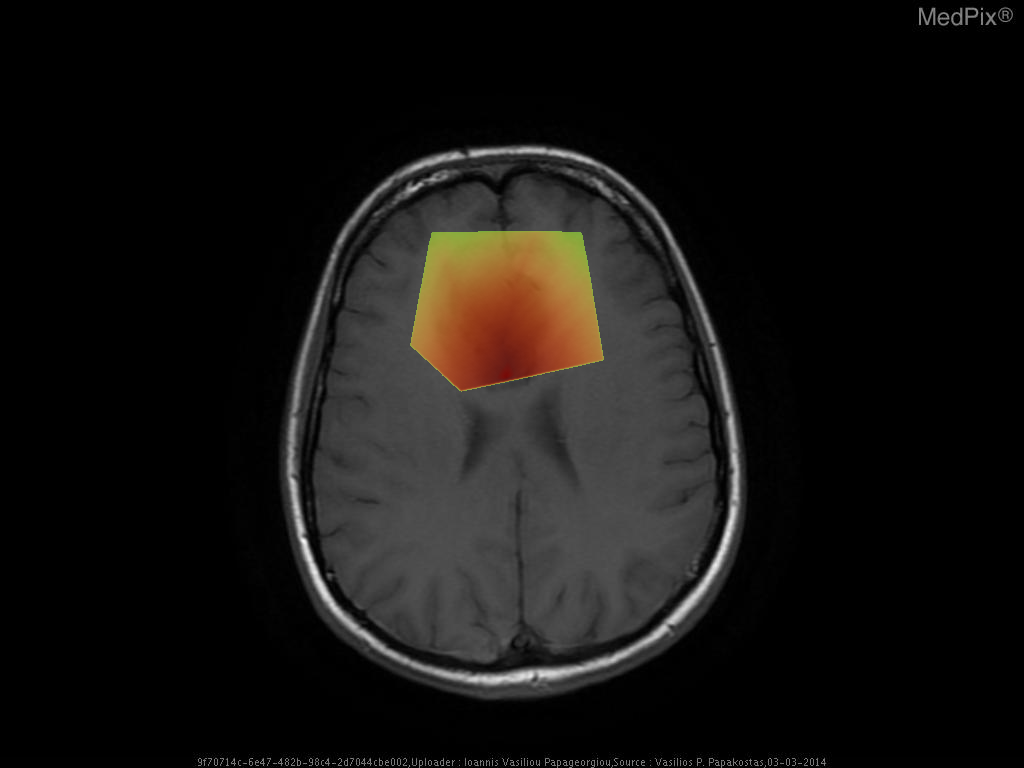

- Axial T1-weighted MRI brain shows a poorly defined, expansile lesion involving the image-right (patient-left) frontal lobe.

- The lesion demonstrates low T1 signal intensity relative to normal cortical gray matter.

- Minimal or no associated enhancement or hemorrhage visible on this non-contrast sequence.

- Mild mass effect evidenced by effacement of adjacent cortical sulci and mild displacement of the local midline toward image-left (patient-right).

- Gray-white differentiation appears blunted within the lesion region, suggesting infiltrative rather than circumscribed growth.

- No overt necrosis, cystic change, or intralesional hemorrhage visible on this slice.

- Surrounding brain parenchyma shows mild T1 hypointensity, potentially reflecting mild edema or infiltration.

- Ventricles appear slightly compressed on the image-right (patient-left) side, consistent with localized expansile mass effect.

Low-grade diffuse astrocytoma (WHO Grade

2). This is favored because of the nonenhancing, poorly marginated, T1-hypointense and mildly expansile frontal lobe lesion without necrosis or hemorrhage—classic for a diffusely infiltrative glioma of low grade. Lack of enhancement or necrosis argues against high-grade glioma. Context consistency:

Consistent — the provided context aligns well with the imaging findings of a low-grade diffuse astrocytoma. Confidence: 90%.